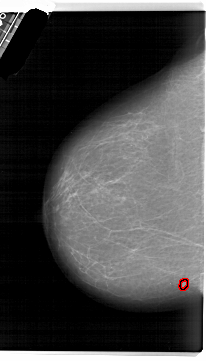

A_1639_1.RIGHT_MLO

RIGHT_MLO LINES 5971 PIXELS_PER_LINE 3856 BITS_PER_PIXEL 12 RESOLUTION 43.5 NON_OVERLAY